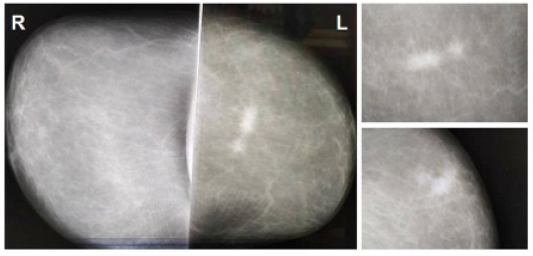

She consulted for a nodule in the left breast of two months of evolution. On clinical examination, a nodule of approximately 5x3 cm was palpated in the upper external quadrant, adhered to the skin and not to deep planes; the armpit was negative on palpation. Mammography revealed two masses of 2 and 1 cm, highly suspicious of malignancy (BI-RADS 5) (Figure 1).

Figure 1: Mammography (BI-RADS 5): Two nodular formations of 2 and 1 cm, very close to each other; with an indefinite contour, irregular shape, high density and surrounded by a peritumoral halo.